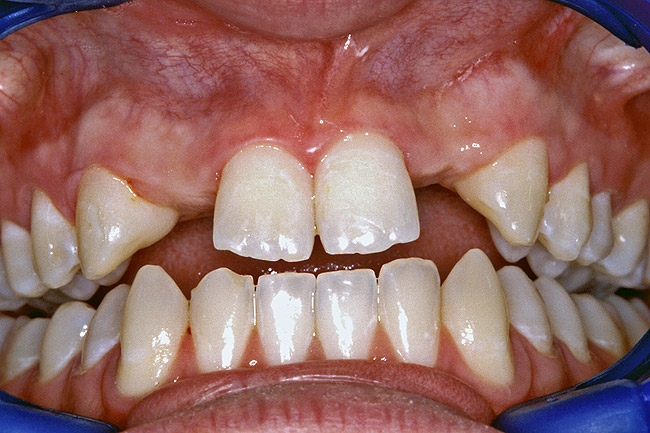

Before the day of surgery, the patient was seen by the orthodontist for the removal of the orthodontic brackets. The patient still was not pleased with the position of the two centrals, and it was determined that this would be addressed after implant placement (Figure 13A). The anatomical variations of the crestal tissue and lack of interdental papilla can be appreciated in the close-up views of the right and left sites (Figure 13B and 13C). There were no surprises on the day of surgery as all of the decisions were made during the planning phase, before the scalpel ever touched the patient. The occlusal view of the CT 3D model revealed the wider alveolar ridge on the right side and thinner crest on the left side (Figure 14A). This was confirmed when the full thickness mucoperiosteal flaps were elevated, and the underyling bone revealed (Figure 14B). The tooth-borne templates were designed to facilitate the drills and drilling sequence specific to the diameters of the predetermined implants (Figure 15A). Each template contained an embedded 5-mm long stainless steel tube, which was approximately 0.2-mm wider than each drill (just wide enough to allow for the drills to rotate freely). Once positioned over the natural teeth, the template was secure and offered precision accuracy in transferring the implant locations from the original software-designed plan, allowing the potential for internal and external irrigation (Figure 15B). The 3.7-mm diameter Tapered Screw-Vent implant drilling sequence requires three drills: pilot, intermediate, and final sizing. Thus, three separate templates were fabricated to a.commodate these sizes. The templates were removed easily and replaced with the next sequential size in less time than it takes to change the drill on the surgical handpiece. After the osteotomies had been.completed, the implants were delivered to the site (Figure 16A and Figure 16B). For this internal hex connection implant, the author r.commends that the flat of the antirotational hex be positioned to the facial for proper orientation of the restorative.components (Figure 17A). Preprepared margins were created from a milled titanium fixture mount transfer post, which was delivered to the implant as support for an immediate transitional restoration. The facial “dot” helped confirm the orientation of the abutment to the facially positioned flat side of the internal hex connection (Figure 17B). Before cementation of the transitional acrylic restorations, a closed-tray, fixture-level impression was made, and a soft-tissue model fabricated.

Figure 13a  Before implant surgery, the orthodontic brackets were removed, revealing (A) the position of the centrals, and (B, C) the anatomical variations of the crestal tissue and lack of interdental papilla.

Figure 13a

Figure 13b  Before implant surgery, the orthodontic brackets were removed, revealing (A) the position of the centrals, and (B, C) the anatomical variations of the crestal tissue and lack of interdental papilla.

Figure 13b

Figure 13c  Before implant surgery, the orthodontic brackets were removed, revealing (A) the position of the centrals, and (B, C) the anatomical variations of the crestal tissue and lack of interdental papilla.

Figure 13c